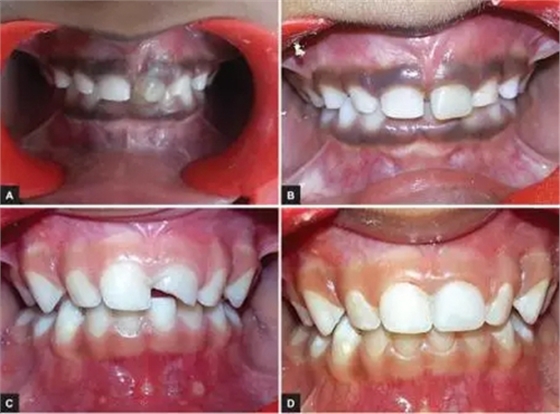

本研究中,其他患齲齒或牙外傷的患兒均采用此方法使用臨時冠材料進行美學修復,下圖分別為兩例乳前牙齲齒(圖2)和兩例牙外傷(圖3)的病例。

圖3.(3-A,3-B為乳前牙外傷病例1 3-C,3-D為乳前牙外傷病例2)